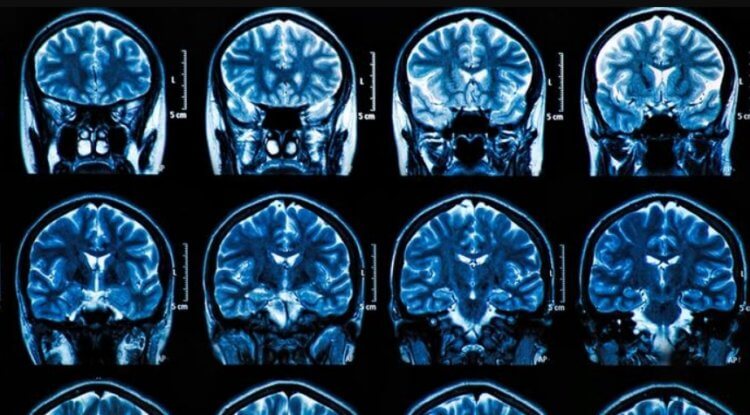

SARS-CoV-2 betrifft verschiedene menschliche Organe, einschließlich des Gehirns

Coronavirus verursacht einen entzündlichen Prozess, der das Gehirn zerstört

Coronavirus zerstört Neuronen in verschiedenen Teilen des Gehirns

Maura Boldrini, Neurowissenschaftlerin und Psychiaterin an der Columbia University in Manhattan, war eine der ersten, die das Gehirn von Menschen und Tieren untersuchte, die an COVID-19 gestorben sind. Unter dem Mikroskop fanden Boldrini und ihr Team Veränderungen im Hippocampus, einem Bereich des Gehirns, der tief im Schläfenlappen liegt und eine wichtige Rolle beim Lernen und Gedächtnis spielt. Nach der Krankheit war die Zahl der neuen Neuronen in diesem Teil des Gehirns zehnmal geringer als sie sein sollte.

Das Team fand auch Schäden an der Medulla, die Atmung und Bewegung kontrolliert. Andere Forscher fanden Hinweise auf Gewebeschäden an der dünneren Kortikalis und den Verlust der grauen Substanz. Die Autoren stellten fest, dass Krankenhauspatienten einen deutlich größeren kognitiven Rückgang erlitten als Patienten mit einem leichten Coronavirus.

Wissenschaftler haben auch festgestellt dass Schlüsselzellen im Gehirn, Astrozyten genannt, anfällig für eine direkte Infektion durch das Virus sind. Darüber hinaus kann das Virus den Blutfluss zu Neuronen beeinträchtigen, indem es Kapillaren, also winzige Blutgefäße, verengt. Dies könnte erklären, warum das Virus häufig Schlaganfälle verursacht.